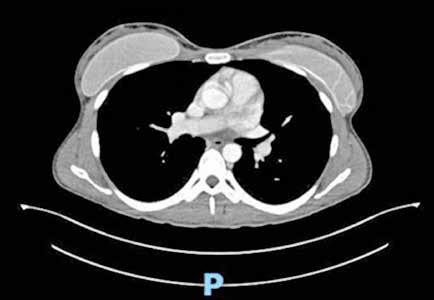

Es ingresado en Medicina Interna en mayo de 2022 por cuadro de fiebre de origen no filiado acompañado de astenia crónica y artralgias múltiples (especialmente en hombro izquierdo). Se administra ceftriaxona intravenosa con buena evolución del proceso febril. No se aísla ningún microrganismo en estudio microbiológico. En el análisis sanguíneo al ingreso destacan los siguientes valores: Hemoglobina 9,1 g/dL; Volumen Corpuscular Medio 105,5 u^3; Leucocitos 8200/L; Neutrófilos 6900/L; Plaquetas 64000/L. En la morfología de sangre periférica se observaban hematíes en lágrimas. Se realiza tomografía computarizada toracoabdominal en el que destaca esplenomegalia de 14 cm, quiste hidatídico hepático y múltiples nódulos milimétricos en ambos lóbulos pulmonares inferiores (Figura 1).

Tras el alta en Medicina Interna es derivado a consulta de Hematología para estudio de anemia no carencial no regenerativa, trombopenia, dacriocitos en sangre periférica y esplenomegalia. Refería fiebre de hasta 38,3ºC los días previos a la consulta, artralgias en múltiples localizaciones y lumbalgia. En la exploración física no se aprecian visceromegalias ni adenopatías. No otros hallazgos significativos en exploración por aparatos. En análisis sanguíneo: Hemoglobina 9,7 g/dL; Volumen Corpuscular Medio 107 u^3; Leucocitos 4300/L; Neutrófilos 1500/L, Monocitos 200/L, Cayados 6%; Metamielocitos 4%; Mielocitos 1%, Plaquetas 104.000/L. Morfología sangre periférica: algún dacriocito aislado. Reticulocitos 2,4%. Filtrado Glomerular